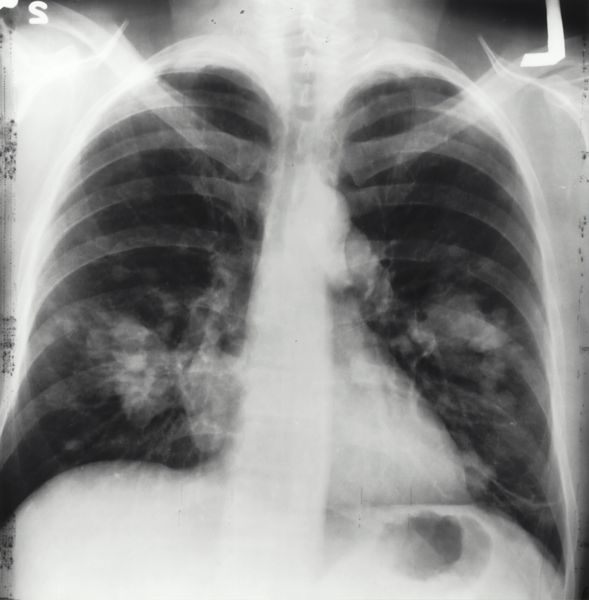

Snarkanningar fyri tarmkrabba

Sum tað er gott, at Sjúkrahúsverkið nú er klárt at fara undir at gera snarkanningar fyri tarmkrabba. Stóra tøkk!

Krabbameinsætlanin verður skjótt fýra ár, og eitt av tilmælunum í henni er at gera snarkanningar fyri tarmkrabba. Í øllum grannalondunum verða hesar kanningar gjørdar.

Tilmælið um snarkanningar fyri tarmkrabba kemur ikki av ongum, tí sum nevnt verður í Krabbameinsætlanini, so er hetta ein av størstu krabbameinsbólkunum.

Danir hava gjørt hesar kanningarnar síðani í 2014. Teir siga, at kanningarnar gera, at 69% av tilburðunum verða funnir so tíðliga, at viðgerðin kann vera nógv mildari. Nýggjastu donsku tølini vísa eisini, at 20% sleppa undan at fáa tarmkrabba, tí undanstig til krabban verða funnin í kanningunum.

Sjúkrahúsverkið fer í fyrstu atløgu undir eina undanverkætlan.

Í Krabbameinsfelagnum vóna vit, at tað gongur ikki long tíð, til vit hava eitt landsstýrisfólk í heilsumálum, sum kann siga: Í Føroyum bjóða vit øllum millum 50 og 74 ár snarkanningar fyri tarmkrabba.